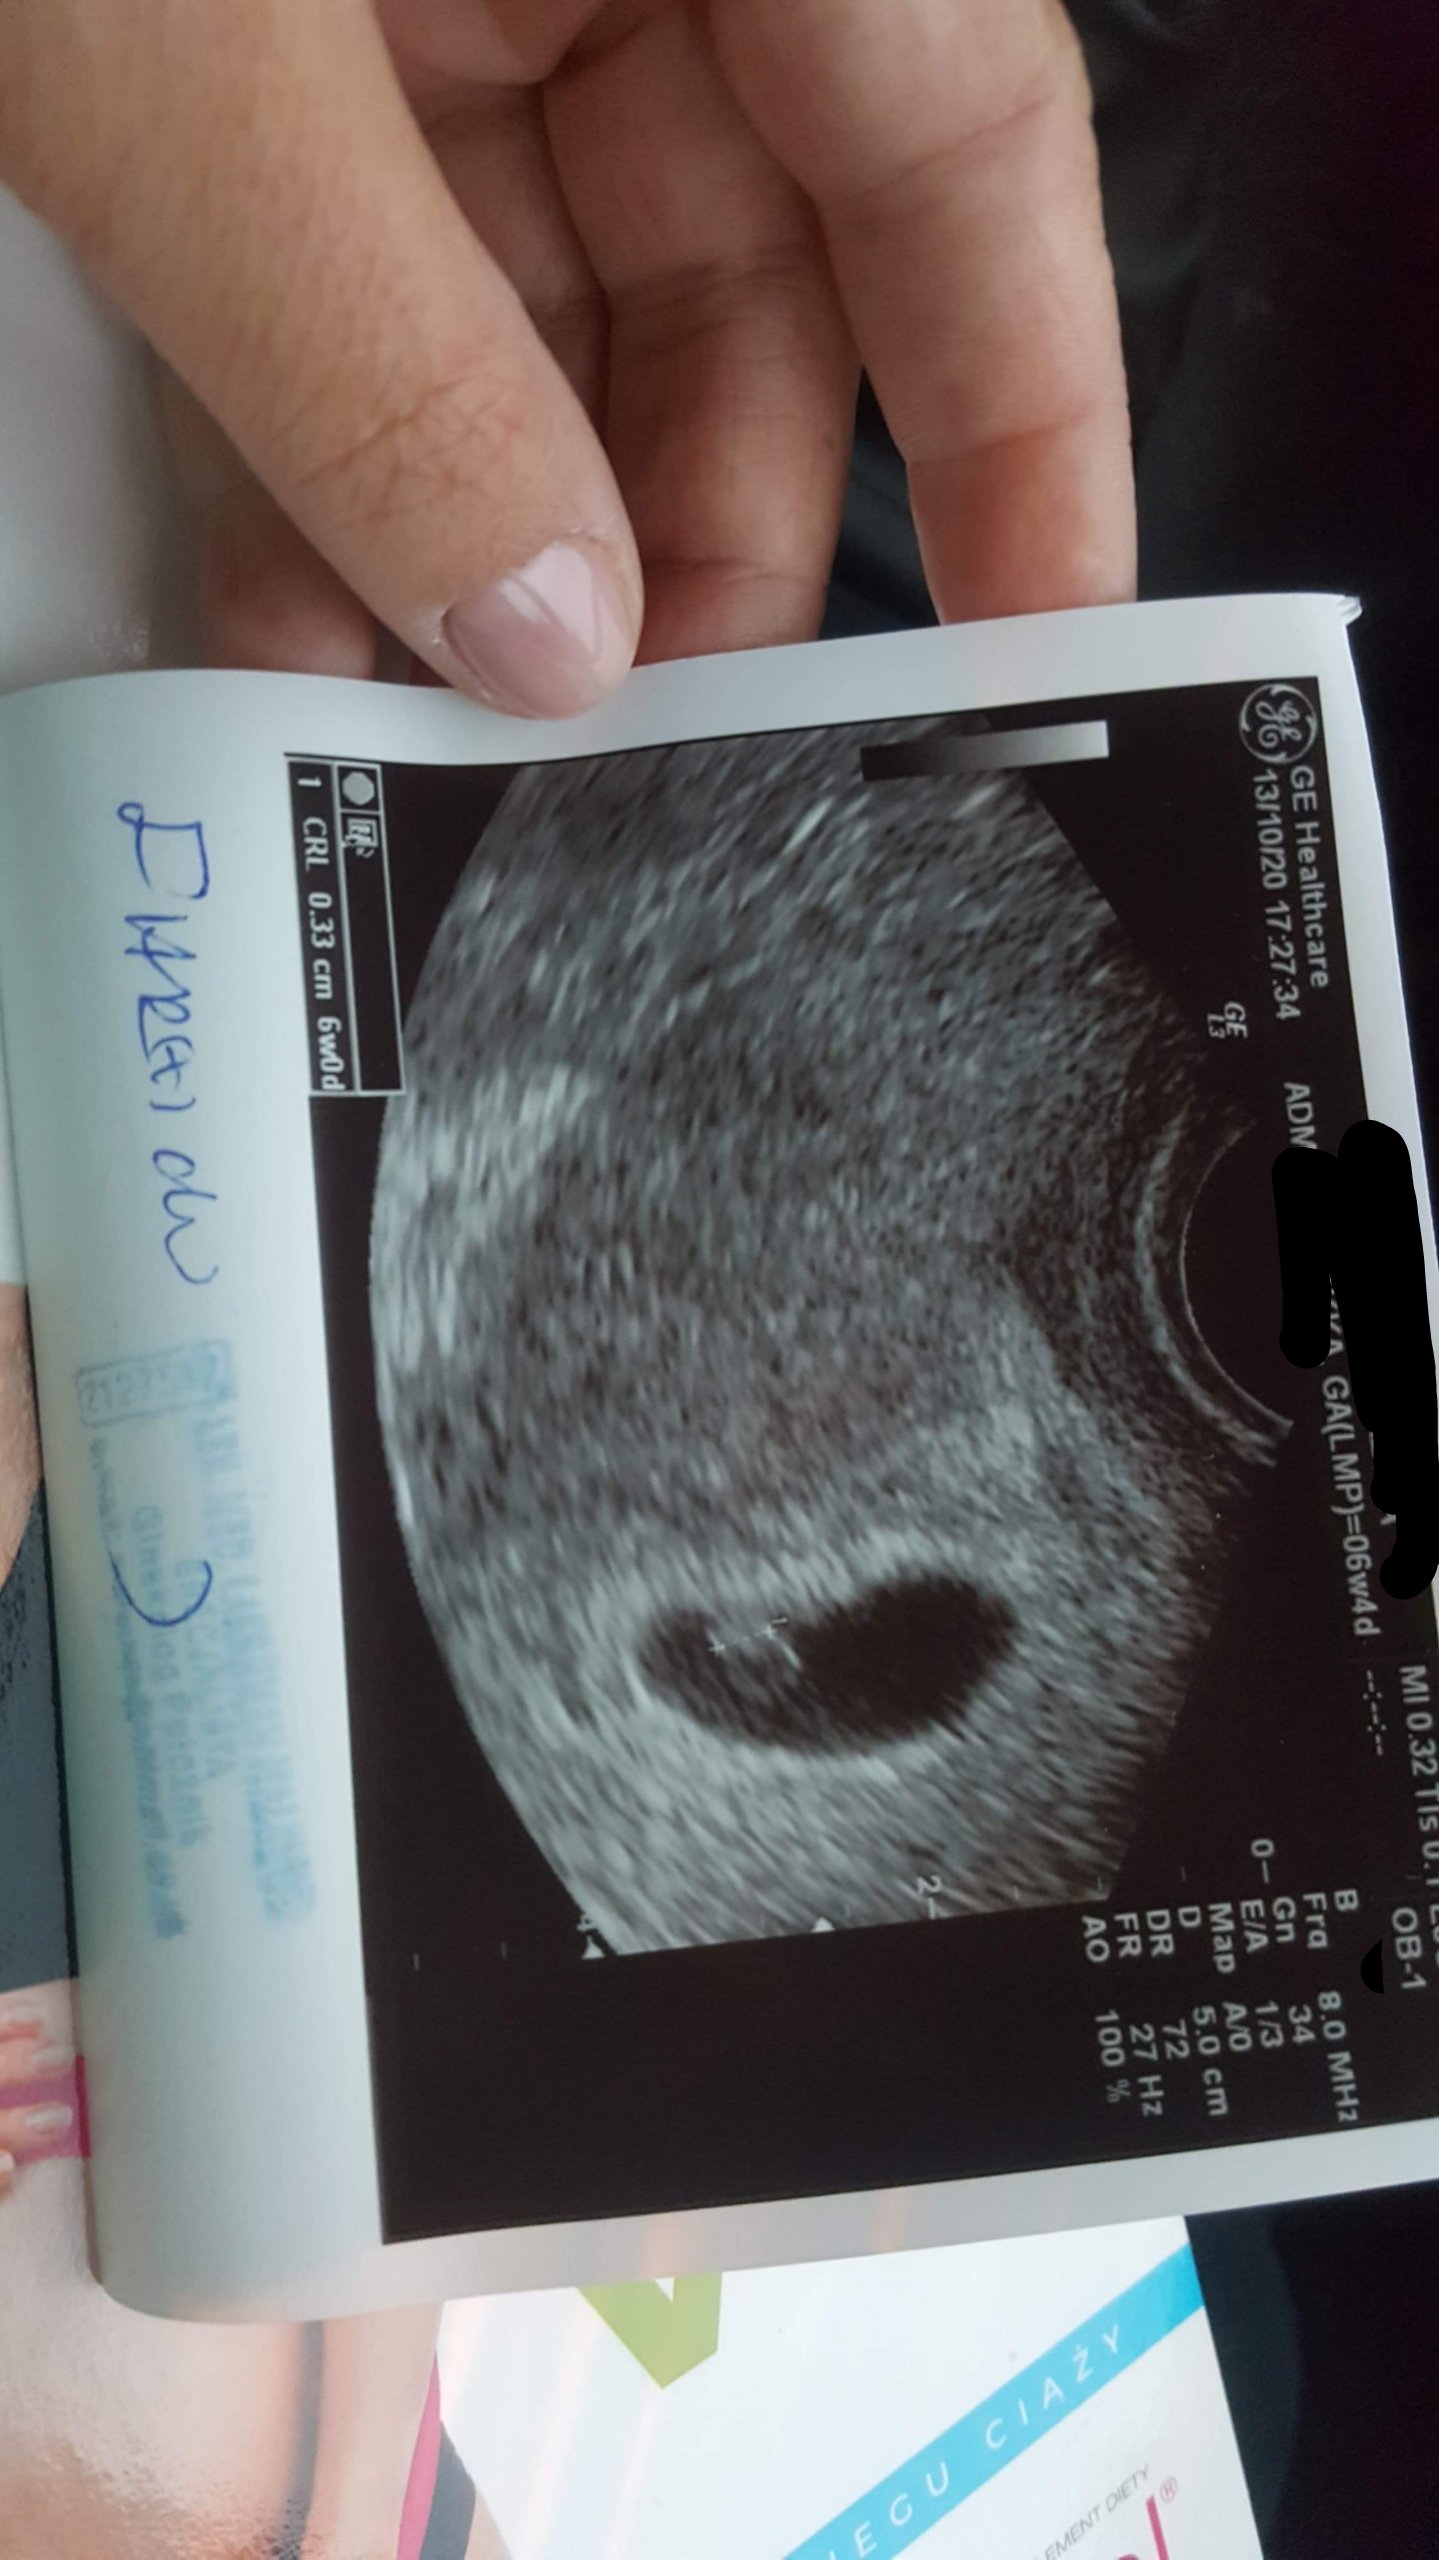

Gratulacje !!!!Kochane ciaza o 4 dni młodsza 6+0 piekny zarodek z bijacym serduszkiem ❤ Nie wierzyłam a jednak!

Kolejne cudowne wieściKochane ciaza o 4 dni młodsza 6+0 piekny zarodek z bijacym serduszkiem ❤ Nie wierzyłam a jednak!

No i brawoKochane ciaza o 4 dni młodsza 6+0 piekny zarodek z bijacym serduszkiem ❤ Nie wierzyłam a jednak!

Kochane ciaza o 4 dni młodsza 6+0 piekny zarodek z bijacym serduszkiem [emoji173] Nie wierzyłam a jednak!